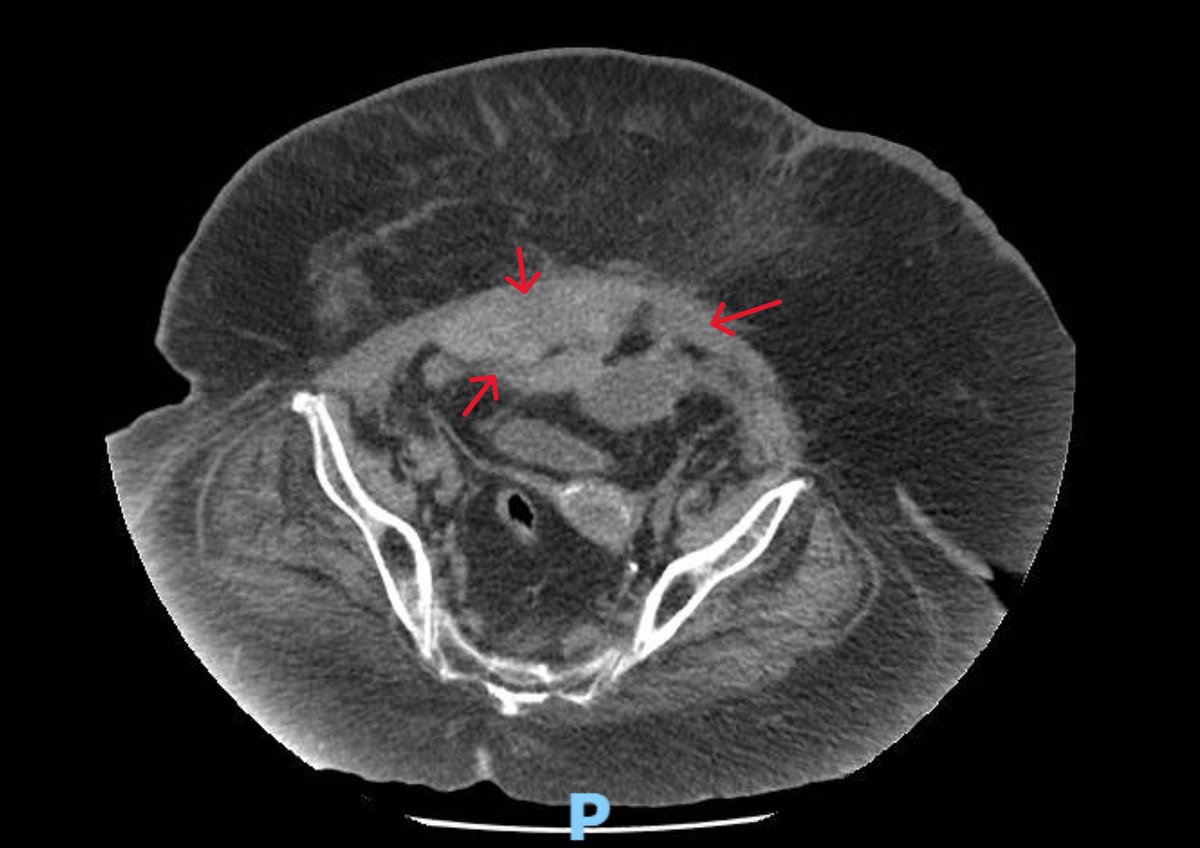

CT abd confirmed an intramuscular and intraperitoneal hematoma. Most probably related to dual antiplatelet and cough

muscular hematoma An 84-year-old with morbid obesity, type 2 resp failure, admitted with acute dropping of hemoglobin to 6 gm and right abdominal pain. POCUS showed right abd muscular huge hematoma